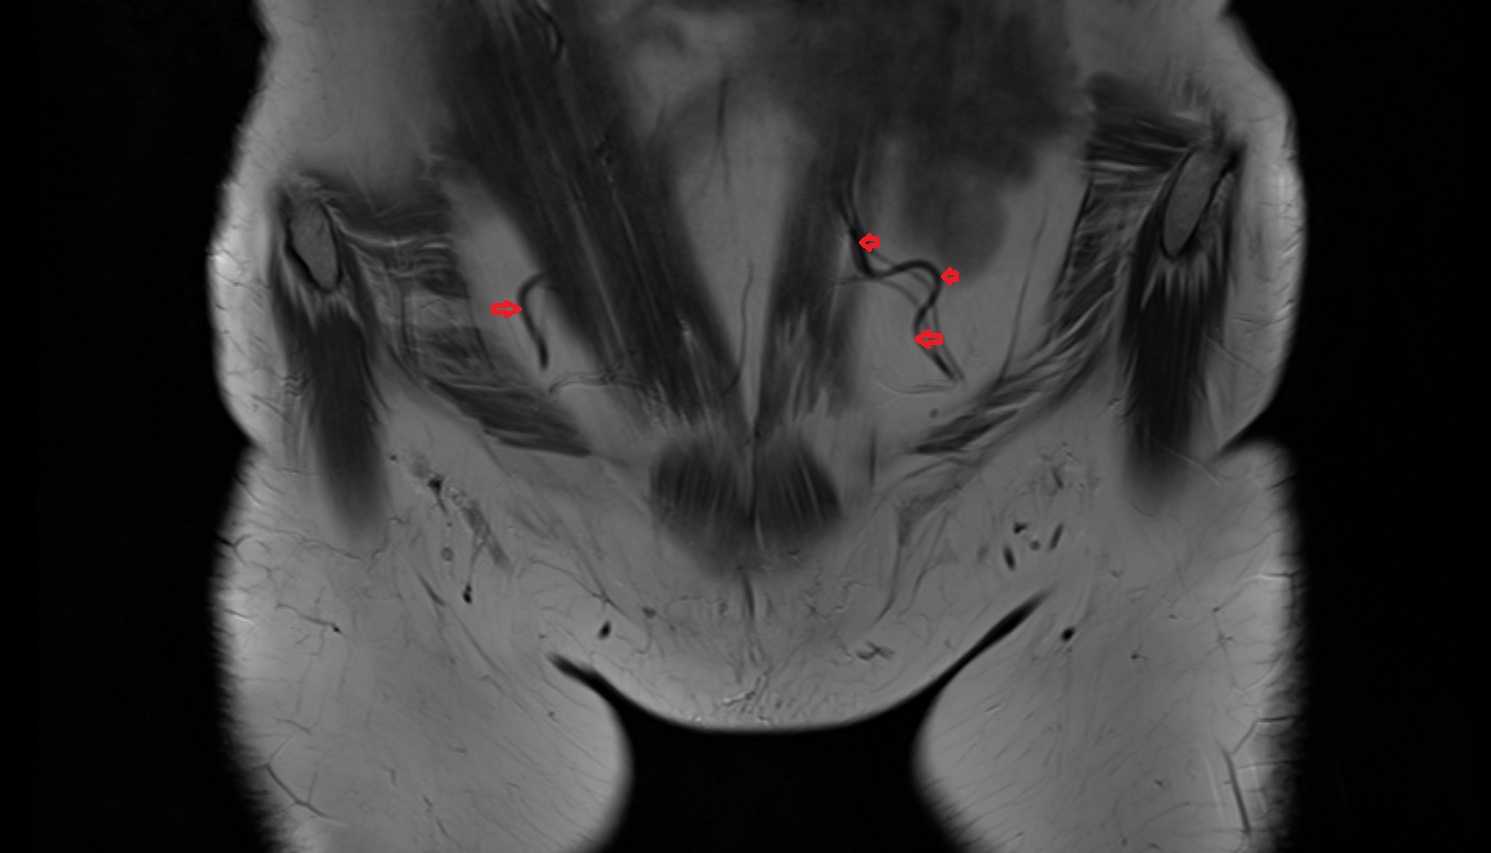

- Inguinal lymph nodes

- External iliac lymph nodes

- Obturator lymph nodes

- Superficial inguinal lymph nodes